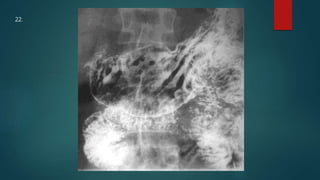

This document appears to be a medical report discussing several patients. It mentions a 35-year-old who was in a severe motor vehicle accident and an 81-year-old with a history of a non-vegetarian diet who had a perforated bowel from a chicken bone. The document provides few other details across its 25 numbered entries and was authored by Dr. Anish Choudhary for junior year 3 on May 30, 2016.